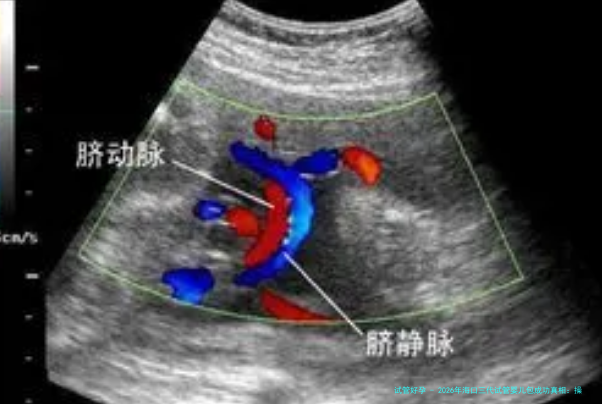

为了取得多个成熟卵子,医生会使用促卵泡发育药物刺激卵巢。促排卵方案的选择因人而异,常见的有长方案、短方案、拮抗剂方案等。在促排卵期间,医生会定期进行B超检查和性激素测定,监测卵泡发育情况,并根据情况调整用药剂量。促排卵过程通常连续8-12天。

当卵泡发育成熟后,医生会在B超疏导下,经阴道穿刺取卵。采卵过程一般来说在麻木下进行,患者不会感到显然的酸痛。拿出的卵子会被立即送往试验室进行处置。

经由遗传学诊断,选择染色体正常或未携带致病基因的胚胎进行移植。在移植前,医生会评估女性的子宫内膜情况,必要时会进行内膜预备。移植操作流程一般来说在B超引导下进行,医生会将胚胎通过细管送进子宫腔内。移植后,病患需要卧床休息,并按照医生要求嘱使用黄体支持药物。